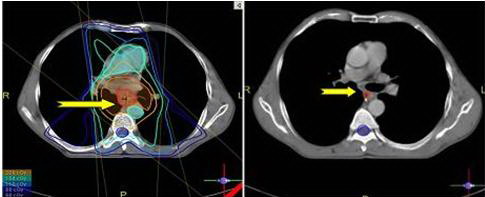

Hình

ảnh khối u trước điều trị và sau điều trị

Trước

điều trị : Khối u kích thước 4,2×3.6cm, kéo dài 5cm, chiếm hết lòng thực

quản gây chít hẹp, máy soi không qua được. Bệnh nhân chỉ có thể uống sữa, không

thể nuốt cháo được.

Sau

điều trị : khối u tan hết, lòng thực quản nhẵn. Bệnh nhân đã ăn cơm được.